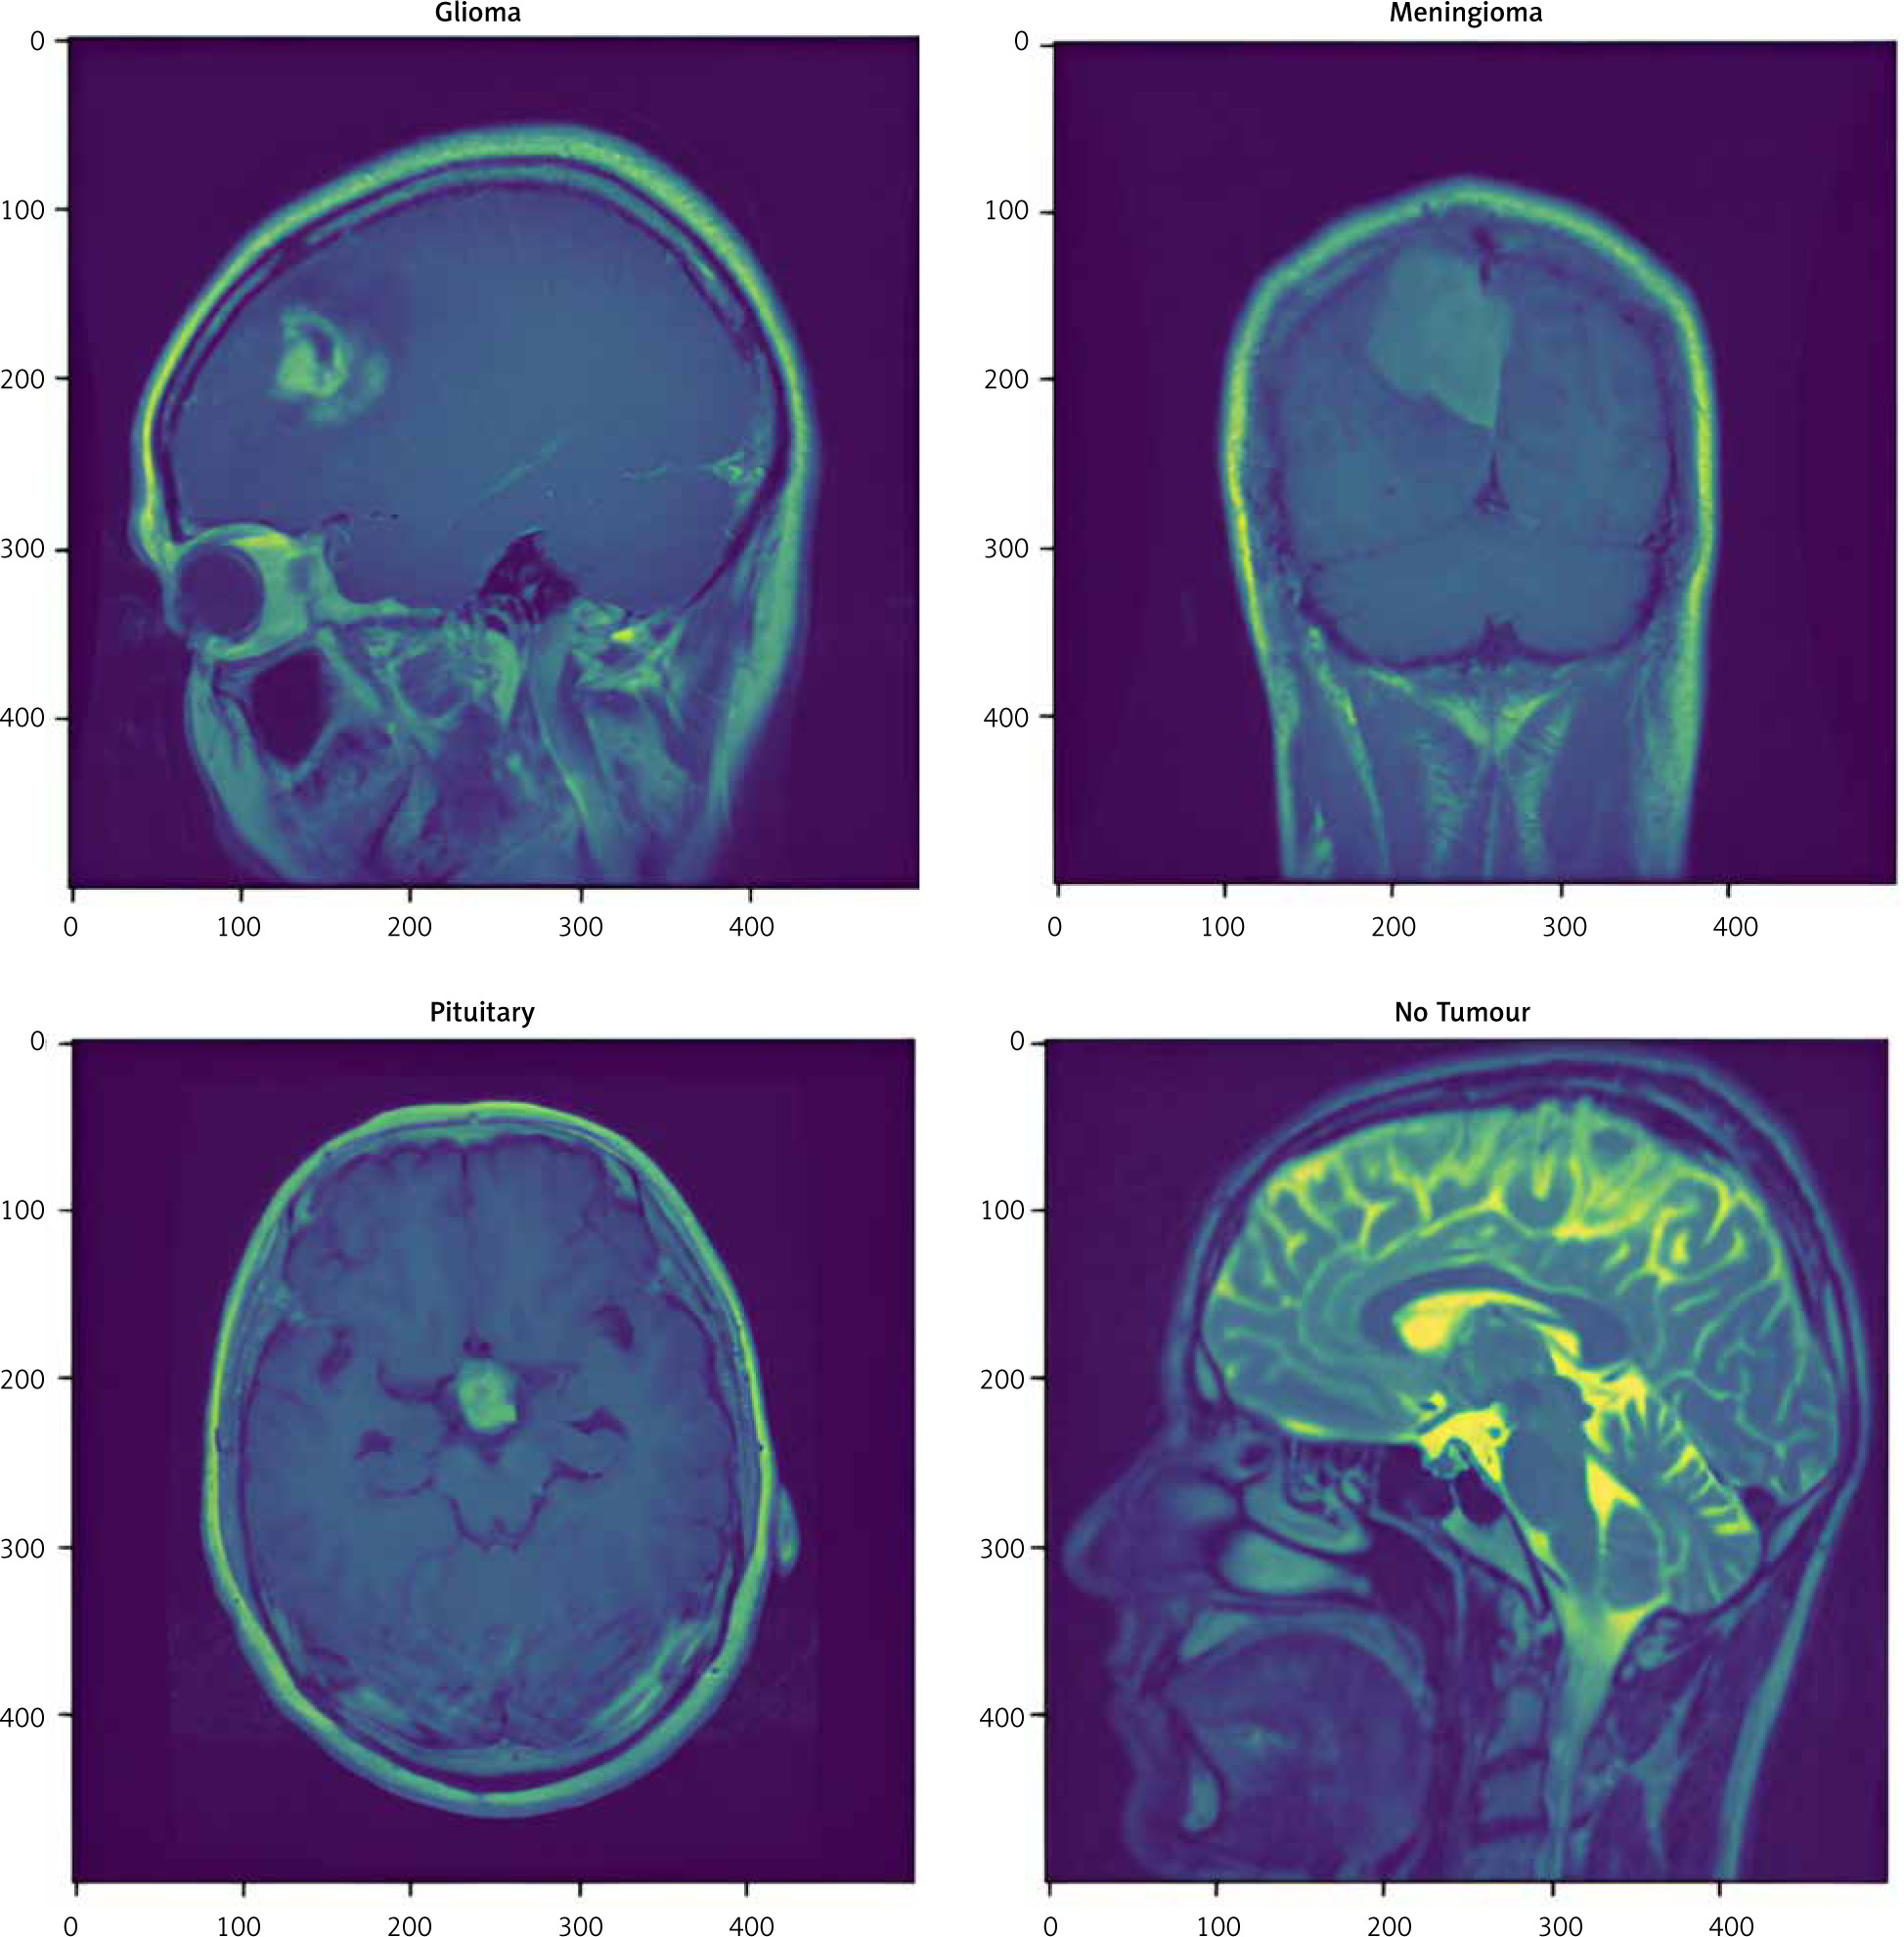

The data used in this work consist of 3264 MRI images, of which 926 are glioma images, 937 are meningiomas, 901 are pituitary gland tumours, and 500 are healthy brains [20]. Figure 1 shows examples of images of the different tumour types. The magnetic resonance imaging from this dataset had different sizes, and because these images represent the input layer of the networks, they were reduced to 100 × 100 pixels. Of the total 3264 data, 80% (2611) were used as training data, and 20% (653) were used as validation data.

Fig. 1

Different samples of magnetic resonance imaging: glioma, meningioma, pituitary tumour, and healthy brain